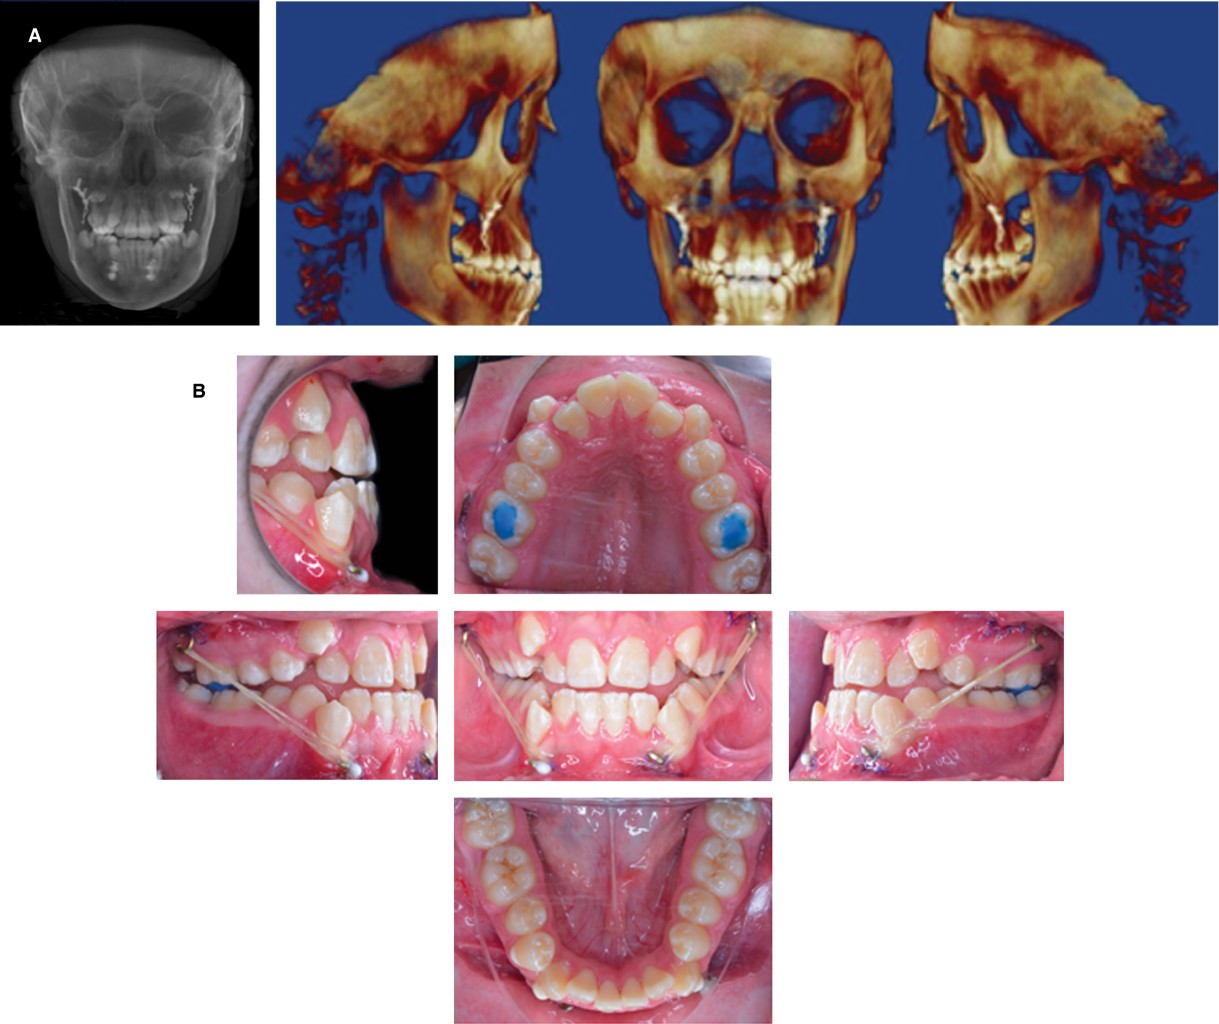

Durante la fase ortopédica se realizó la colocación de las placas de anclaje esqueletal de 2.0 mm de titanio, cada una con dos tornillos de 2.0 × 9 mm colocados en la parte mandibular entre caninos y laterales de ambos lados y en la parte maxilar en el arco cigomático a nivel radicular del segundo molar en ambos lados, el cual es un procedimiento realizado con anestesia general, pero ambulatorio. Al mes del procedimiento quirúrgico se toma una tomografía de haz cónico (Cone Beam) para la evaluación de la osteointegración de las placas y posteriormente hacer la colocación de elásticos clase III con 150 g de fuerza (Figura 4A), en esta fase del tratamiento se colocan turbo bite en primeros molares superiores para lograr la desoclusión anterior y que la mecánica fuera más efectiva junto con los elásticos clase III que se utilizaron por 10 meses (Figura 4B), comenzando con fuerzas ligeras desde los 150 g hasta llegar a los 450 g por lado. Posterior a esto, el paciente presentó una mejor relación maxilomandibular y se continuó con la fase ortodóncica para la corrección de la oclusión (Figura 5).

Figura 4